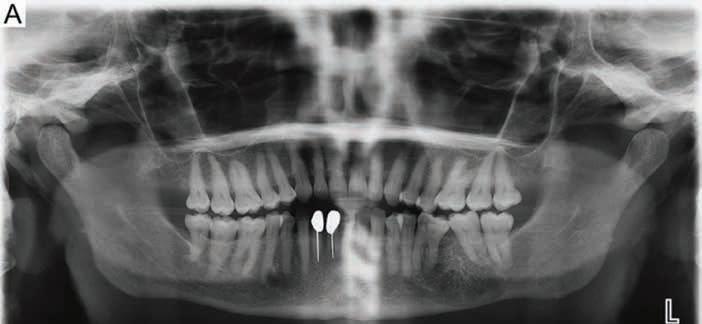

A 62-year-old female presented with a chief complaint of swelling of her left mandible. The patient’s medical history was significant for hypertension and anxiety. Her medications included hydrochlorothiazide and lorazepam. On intraoral examination, a mild expansion of the mandibular buccal cortex in the region of teeth #18-20 was noticed. A panoramic radiograph revealed a well-demarcated radiolucent lesion containing coarse primary trabeculations in the left body of the mandible. The lesion demonstrated a central area of coarse and radiating trabecular bone formation, creating a “spoke-wheel” or “sunburst” appearance. The lesion perforated the inferior cortex of the mandible and caused the displacement of teeth #19 and #20 (Figure 1). A previous panoramic radiograph from 6 years prior to presentation was obtained from her general dentist which showed a similar abnormal bony trabecular pattern near teeth #18-19 with splaying of the roots between teeth #18 and #19 (Figure 1A). However, in comparing the 2 radiographs, it was clear that there had been significant growth of the lesion over the intervening time. Cone-beam computed tomography was then performed which showed a multilocular, lytic lesion containing coarse, internal bone trabeculae and causing buccal expansion of the mandibular cortex and disruption of the lingual cortex (Figure 2). An incisional biopsy was performed.

Figure 1A, 1B. Panoramic radiographs from 2018 and 2024. A) Panoramic radiograph from 2018 showing a large, fairly well-demarcated, radiolucent lesion with faint trabeculations involving the left body of the mandible. B) Panoramic radiograph from 2024 showing a large, welldemarcated, radiolucent lesion with coarse primary trabeculations involving the left body of the mandible. The lesion characteristically produced a centrally localized “spoke-wheel” or “sunburst” pattern of reactive bone formation and displacement of adjacent teeth.